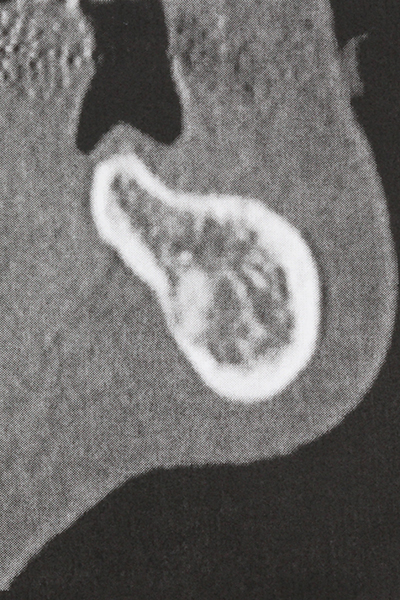

Bei der Knochenblockentnahme zeigen sich weitere Vorteile für die Piezochirurgie: Neben der bereits beschriebenen hohen Präzision bei der Osteotomie stellt sich gerade die Verwendung der dünnen Sägespitzen als besonders materialschonend heraus. Bei der Verwendung insbesondere von Lindemannfräsen sind mit deutlich höheren Entnahmeverlusten durch die dickere Instrumentenspitze zu rechnen (Lakshmiganthan, Gokulanathan et al. 2012). Die insbesondere bei retromolar entnommenen Blocktransplantaten notwendige basale Abtrennung wird durch speziell hierfür vorgesehene rechtwinklige Sägen erleichtert, so dass die Piezochirurgie als präzises, übersichtliches und sicheres Verfahren zur retromolaren Knochenblockgewinnung angesehen wird (Happe 2007) (Abb. 1-12).